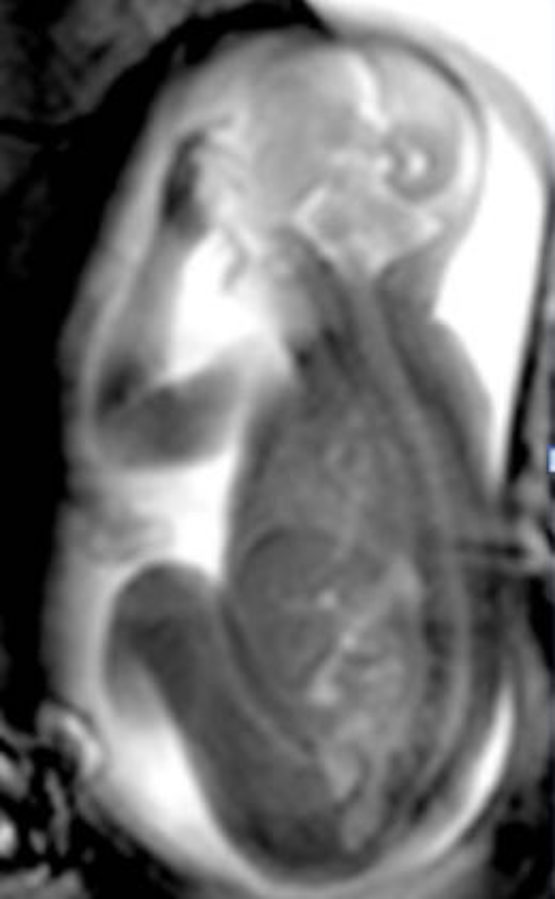

While Rebecca is having her scan, another team of researchers gathers moving images of her baby from a little lab looking into the MRI room through a window. It doesn't look like there's much to see from the window; but on the researchers' screens, Rebecca's body appears in slices. Her digestive organs are squashed around her womb, allowing access to a perfect image of her growing baby.

NewsletterDr Lloyd homes in on Rebecca's stomach, then the baby's miniature version, then mother and child's kidneys and bladders. His trained eye can see the atriums and vessels of the baby's heart. If he can get the right image 'slice', he can spot an abnormality like a vascular ring straight away. The problem with MRI is that when the baby is moving, the image slices don't merge to give a good enough 3D image from which the doctor can diagnose problems.

The team takes multiple images of Rebecca's baby over the course of an hour, making sure to save some video footage to a disc for Rebecca to take home.

We head back up to Dr Lloyd's office. One of the early successes of the iFind project has been applying algorithms to MRI images that can account for a baby's movements. "That's how we managed to make this heart," says Dr Lloyd. "From an MRI scan that we were able to 'correct' to make a 3D model."